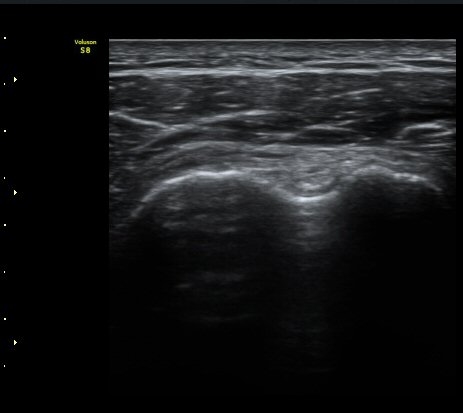

±Ø»ó°Ç Ⱦ´Ü¸é°Ë»ç¿¡¼­ ±Ø»ó°Ç ±ÙÀ§ºÎ¿¡¼­´Â ƯÀÌ ¼Ò°ßÀ» º¸ÀÌÁö ¾ÊÀ¸³ª ±Ø»ó°Ç ¿øÀ§ºÎ¿¡¼­

ÇÇÁú°ñ ¿¬°á ¼Ò½Ç°ú ¹Ì¼¼ÇÑ °ñÆíÀÌ °üÂûµÊ(»çÁø 6, 7).